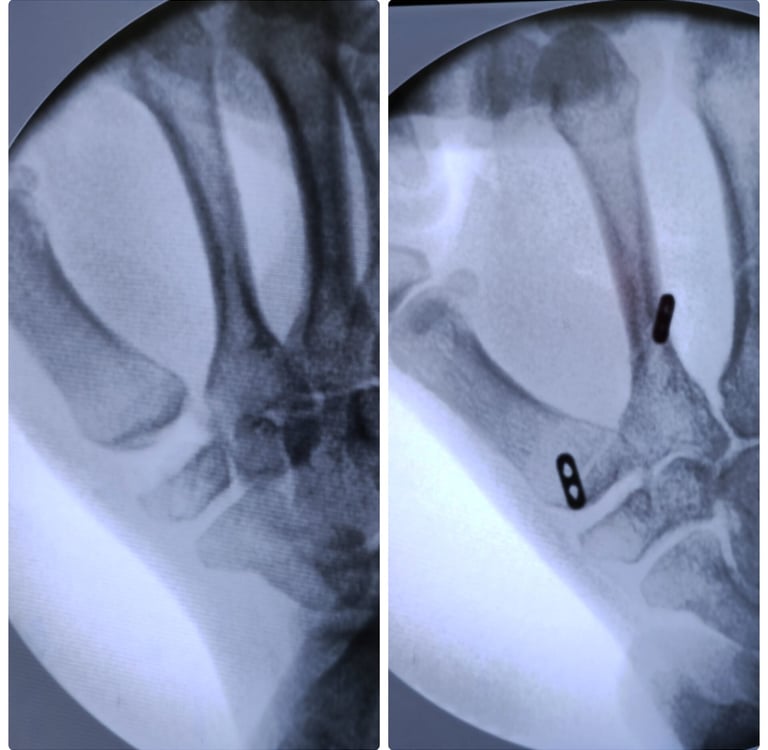

La artroscopia se realiza introduciendo una pequeña cámara (una “óptica”) dentro de la muñeca. Esa cámara nos muestra en una pantalla todo lo que ocurre dentro de la articulación: cartílago, ligamentos, el fibrocartílago triangular (FCT) y cualquier zona dañada.

A través de otros orificios milimétricos se introducen instrumentos finos que permiten reparar, limpiar o tratar la lesión.

Evaluación y tratamiento de fracturas de radio distal o fracturas dentro de la articulación.